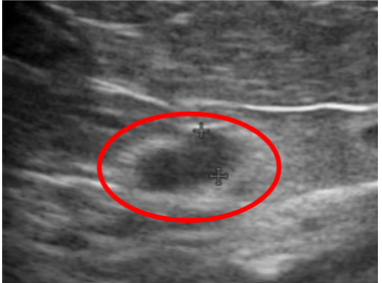

adrenal gland depicted on abdominal ultrasound